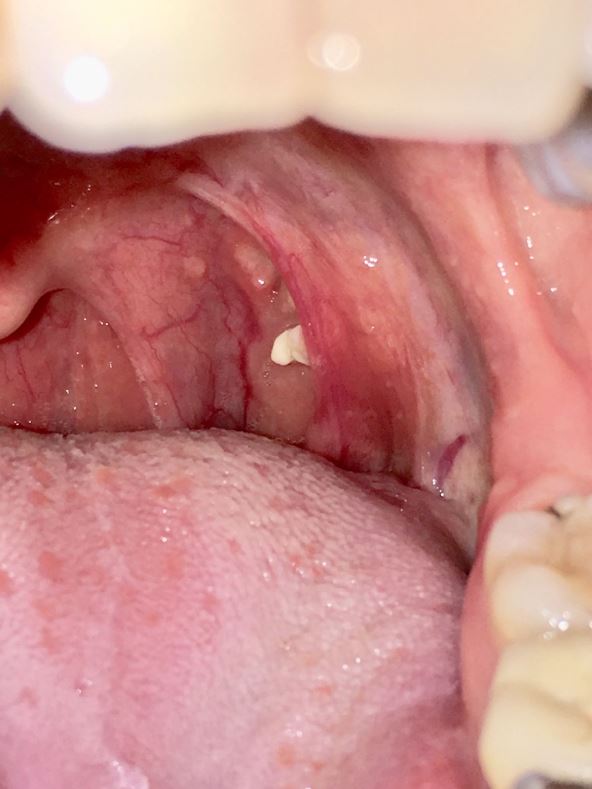

Kamenčići u krajnicima (medicinski naziv: tonziloliti) su male bele ili žućkaste naslage na krajnicima. Nastaju kada se bakterije, pljuvačka, čestice hrane i naslage ćelija iz sluznice usne duplje zarobe u malim udubljenjima zvanim kripte. Njihove karakteristike značajno variraju od osobe do osobe, uključujući:

• Veličinu. Mogu biti toliko mali da se ne vide golim okom, ali mogu narasti do veličine šljunka, a u retkim slučajevima i znatno veći.

• Konzistenciju. Obično su mekani, ali mogu da se kalcifikuju i postanu tvrdi kao kamen - otuda naziv.

• Trajanje. Mogu trajati od nekoliko dana do nekoliko nedelja, a ponekad i znatno duže pre nego što se raspadnu i ispadnu.

• Učestalost. Novi tonziloliti mogu se pojavljivati više puta mesečno ili samo jednom do dvaput godišnje.